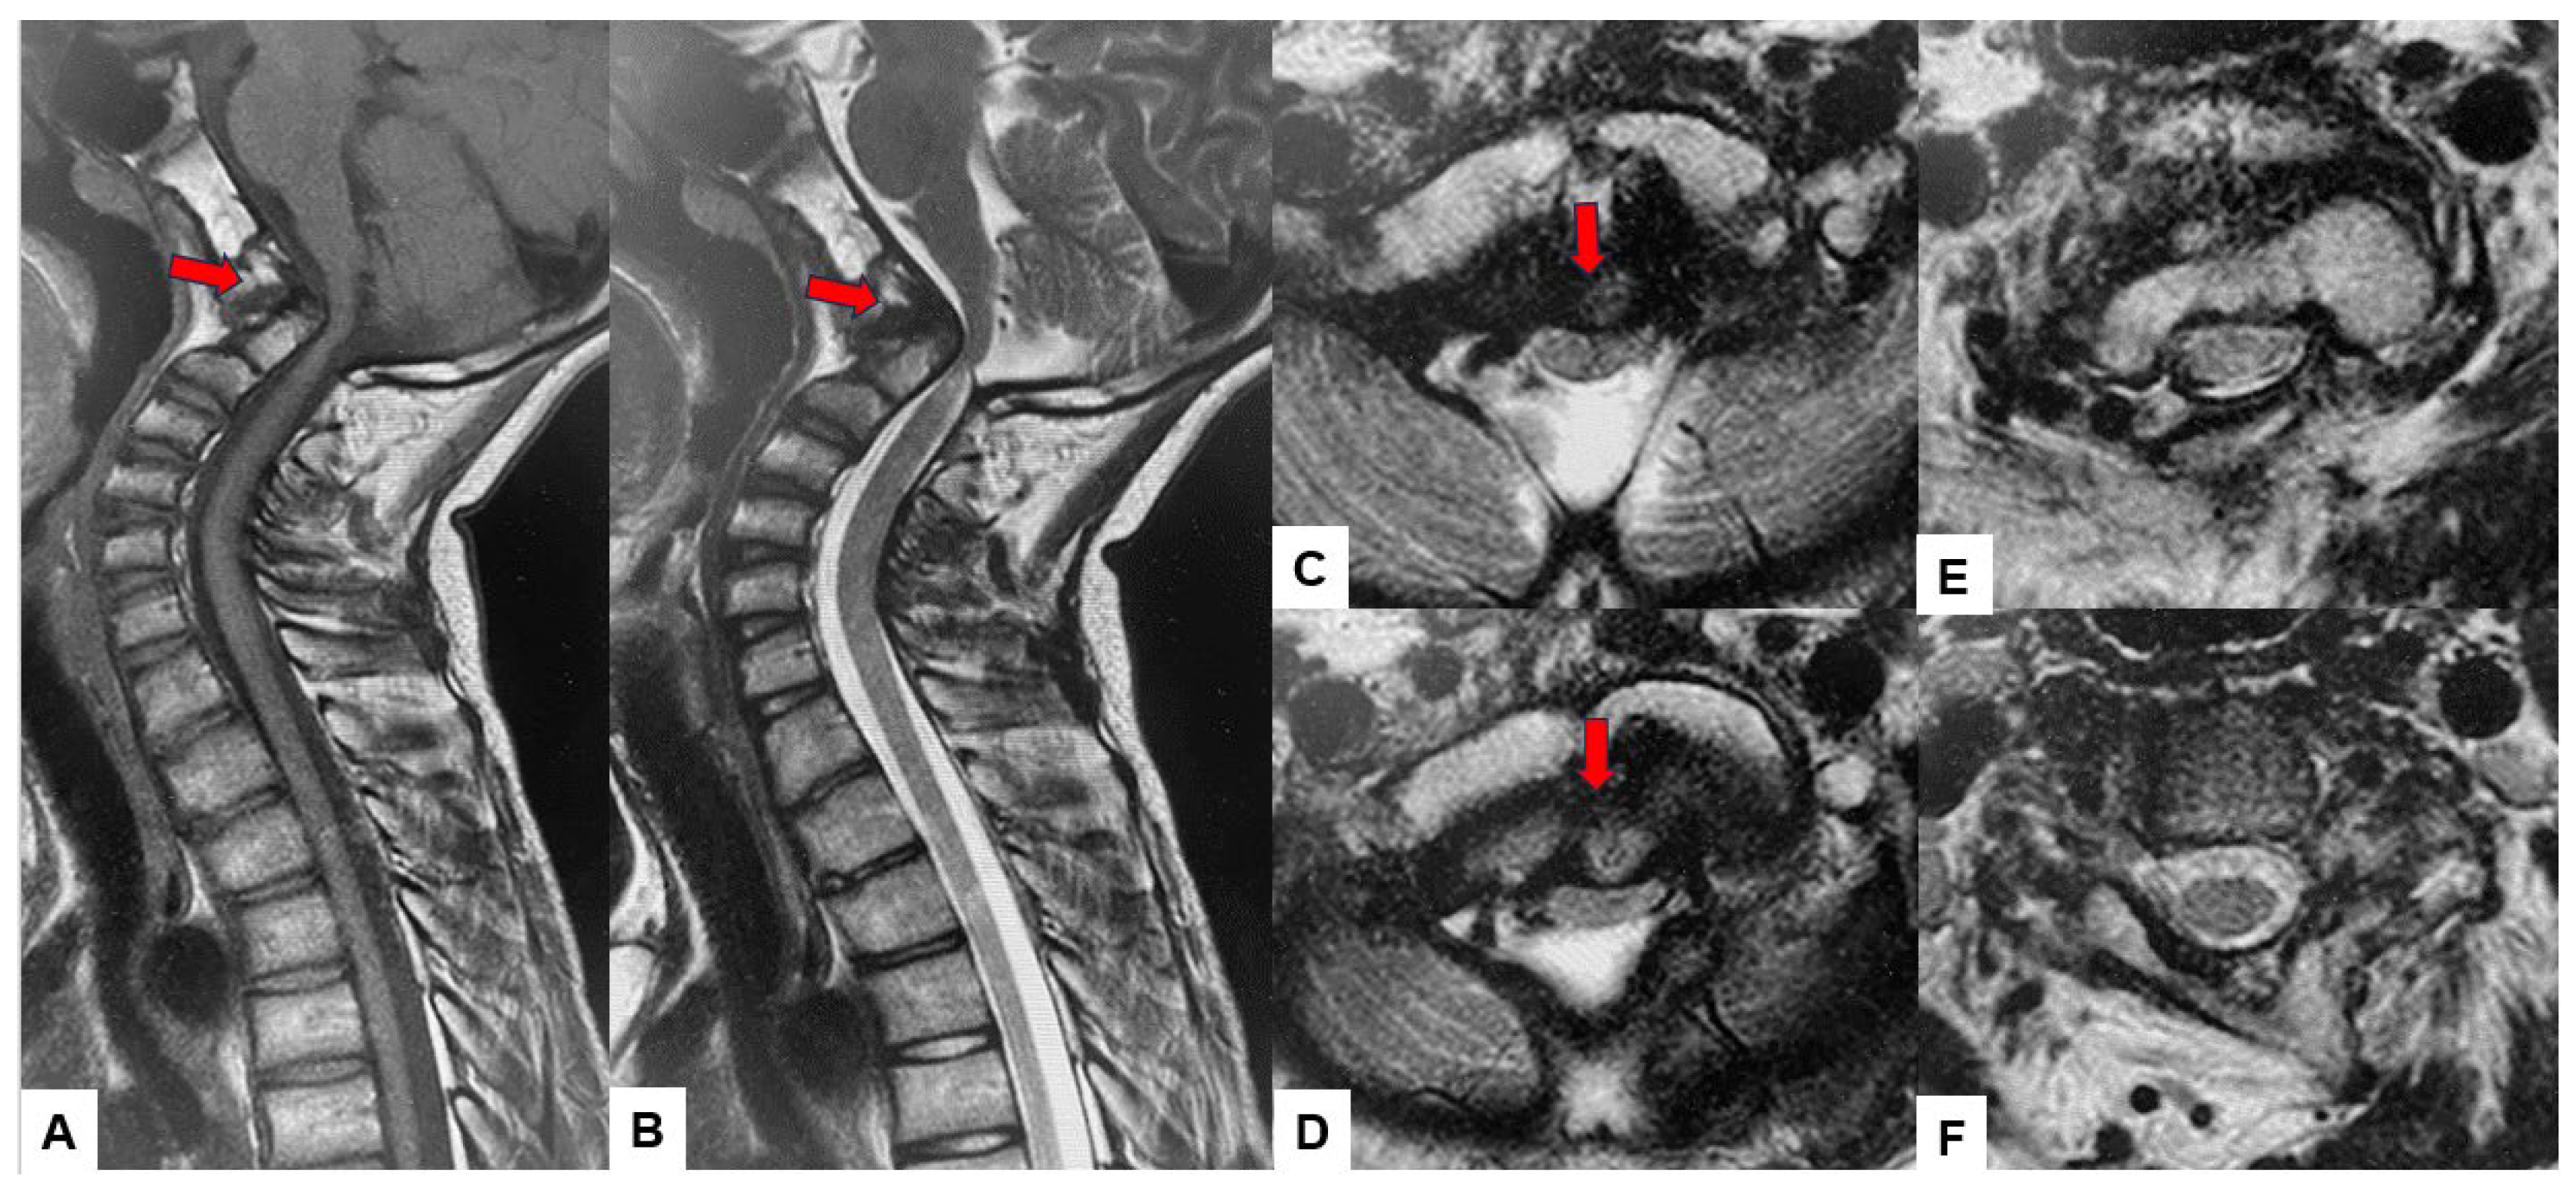

Preoperative cervical radiographs revealed a short neck and a C2/3 fusion anomaly. Dens protrusion into the foramen magnum measured 9.4 mm above McGregor’s line and 4.2 mm above McRae’s line, with an anteroposterior (AP) diameter of the foramen magnum measuring 10.7 mm (Figure 2). Preoperative magnetic resonance imaging (MRI) depicted severe compression of the cervicomedullary cord by the dens, with a cervicomedullary angle (CMA) measuring 116 degrees (Figure 3).

Figure 3.

Preoperative MR imaging, (A) T1 weighted mid-sagittal MR imaging, (B) T2 weighted mid-sagittal MR imaging, (C) T2 weighted axial MR imaging at C1, (D) T2 weighted axial MR imaging at C1-2, (E) T2 weighted axial MR imaging at C2, (F) T2 weighted axial MR imaging at C3. The spinal cord was compressed severely due to basilar invagination. The red arrows show severe compression of the cervicomedullary cord by the dens.